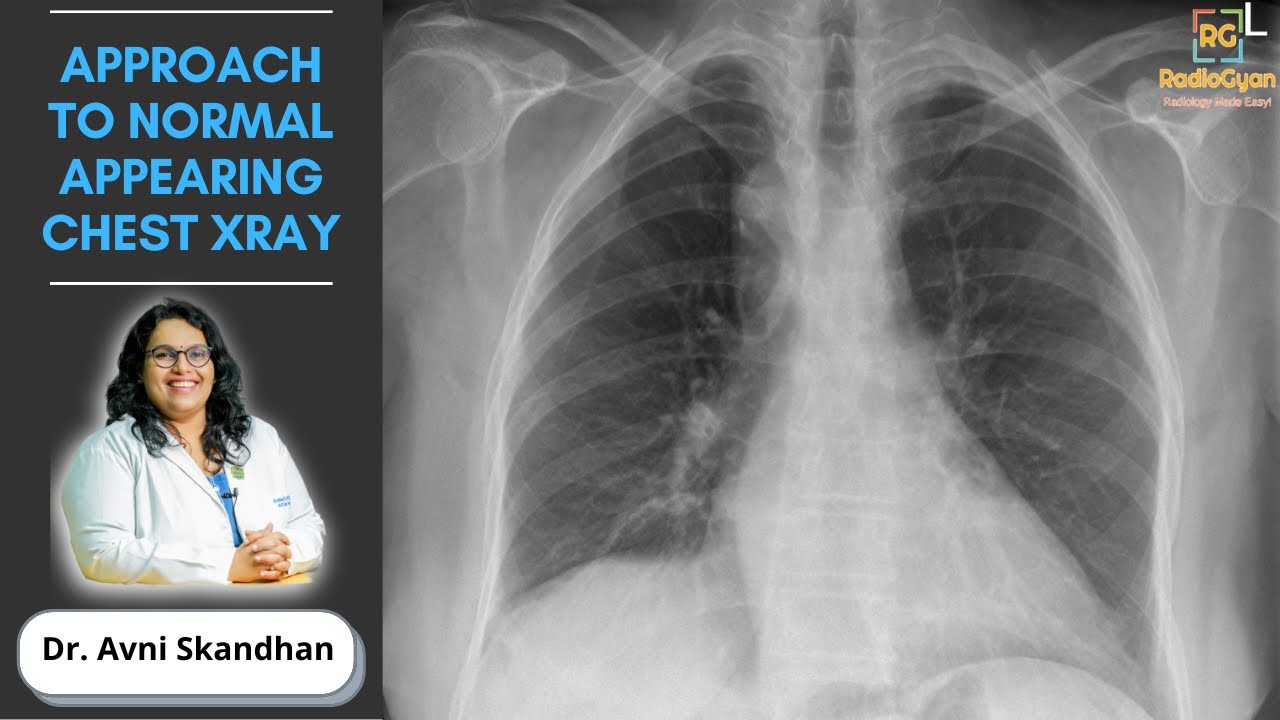

Approach to an Unremarkable Chest X-Ray | Dr. Avni Skandhan